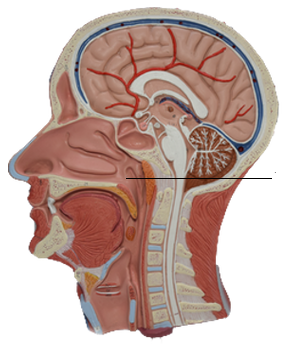

Genioglossus

Hyoglossus

Palatoglossus

Styloglossus

Hard palate

Soft palate

Uvula

Palatoglossal arch

Palatine tonsils

Entrance to auditory tube